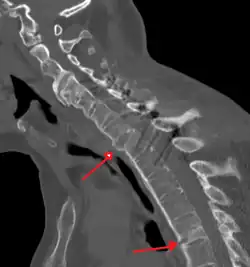

The earliest changes demonstrable by plain X-ray shows erosions and sclerosis in sacroiliac joints. Progression of the erosions leads to widening of the joint space and bony sclerosis. X-ray spine can reveal squaring of vertebrae with bony spur formation called syndesmophyte. This causes the bamboo spine appearance. A drawback of X-ray diagnosis is the signs and symptoms of AS have usually been established as long as 7–10 years prior to X-ray-evident changes occurring on a plain film X-ray, which means a delay of as long as 10 years before adequate therapies can be introduced.[25]

-

Lateral X-ray of the mid back in ankylosing spondylitis -

Lateral X-ray of the neck in ankylosing spondylitis -

X-ray showing bamboo spine in a person with ankylosing spondylitis -

CT scan showing bamboo spine in ankylosing spondylitis -